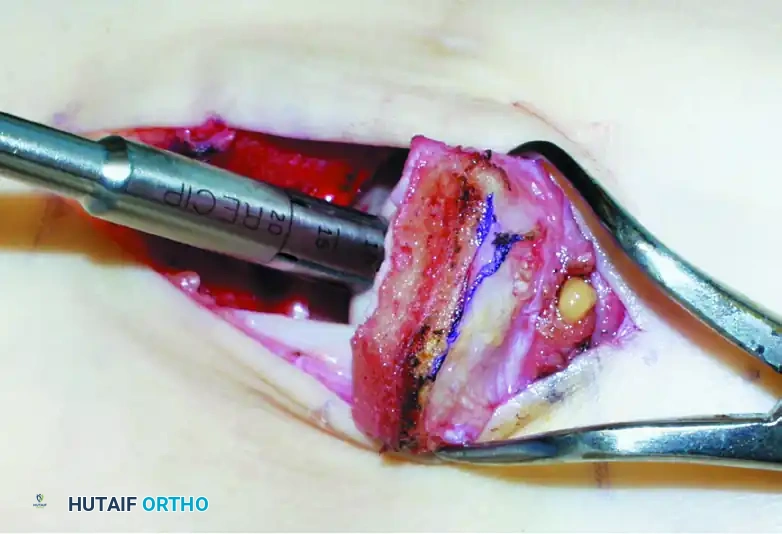

1. Medial Malleolar Osteotomy (For Medial Lesions)

Medial lesions are typically located centrally or posteriorly on the medial talar dome. A medial malleolar osteotomy provides unparalleled perpendicular access.

- Make a longitudinal incision over the medial malleolus.

- Expose the medial malleolus, protecting the posterior tibial tendon and neurovascular bundle posteriorly.

- Pre-drill two holes for 4.0-mm partially threaded cancellous screws to ensure perfect anatomic reduction during closure.

- Perform a chevron-type or step-cut osteotomy using an oscillating saw, completing the final articular cut with an osteotome to preserve the cartilage.

- Reflect the medial malleolus inferiorly on its deltoid ligament hinge.

Step 1: Recipient Site Preparation

Once the lesion is fully exposed, utilize a commercially available recipient sizer to determine the exact diameter of the defect. Harvesters are typically available in sizes ranging from 5 to 11 mm (larger sizes are available for massive defects, though multiple overlapping plugs—the "snowman" technique—may be used).

Place the recipient harvester strictly perpendicular to the articular surface for dome lesions, or at a 45-degree angle for talar shoulder lesions.

Impact the tubular chisel to extract the recipient core to a precise depth of 10 mm. Remove the core, leaving a perfectly cylindrical defect. Drill multiple small holes into the subchondral bone at the base of the recipient hole to stimulate marrow bleeding and enhance graft integration.